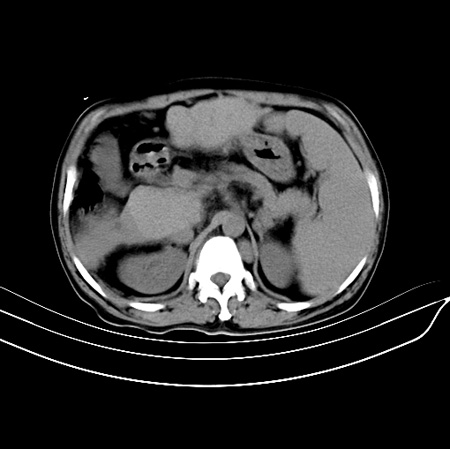

以下是引用江尾海头在2007-9-7 19:01:00的发言:[br]肝叶比例失调,肝边缘高低不平,尾状叶增大,肝裂增宽。肝右叶见较大密度减低影,边缘欠清。脾脏明显增大,胃底及奇静脉半奇静脉曲张。胆囊未见明显显示。 考虑:1、肝癌。2、肝硬化伴脾大静脉曲张。

以下是引用zhangxu5888在2007-9-7 22:31:00的发言:[br]1、肝硬化,食管 胃底及奇静脉半奇静脉曲张;2、脾脏肿大; 3、肝右叶的病灶呈锲性改变,内可见条片状钙化,边界清晰,密度明显低于周围正常肝组织,我觉得肝癌可能性不是很大, 同意楼上观点,有可能是栓塞,建议增强.